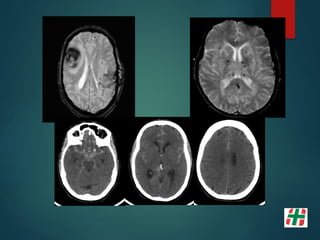

Patología Aneurismática

 Dilatación vascular que afecta solo una porción del

perímetro vascular.

 Carece de lámina elástica y ± túnica media.

 Se los clasifica básicamente en:

 Sacular;

 Ampollar;

 Fusiforme.

Métodos diagnósticos

 Angiografía Digital (3D DSA);

Sensibilidad del 96% lesiones del 0.5 a 4 mm.

 TC, Angio TC (Multidetector);

Sensibilidad del 40% al 97%.

 Angio RM (T.O.F.)

Sensibilidad 38% lesiones al 94%

ARTIFICIOS POR MATERIAL DE EMBOLIZACIÓN